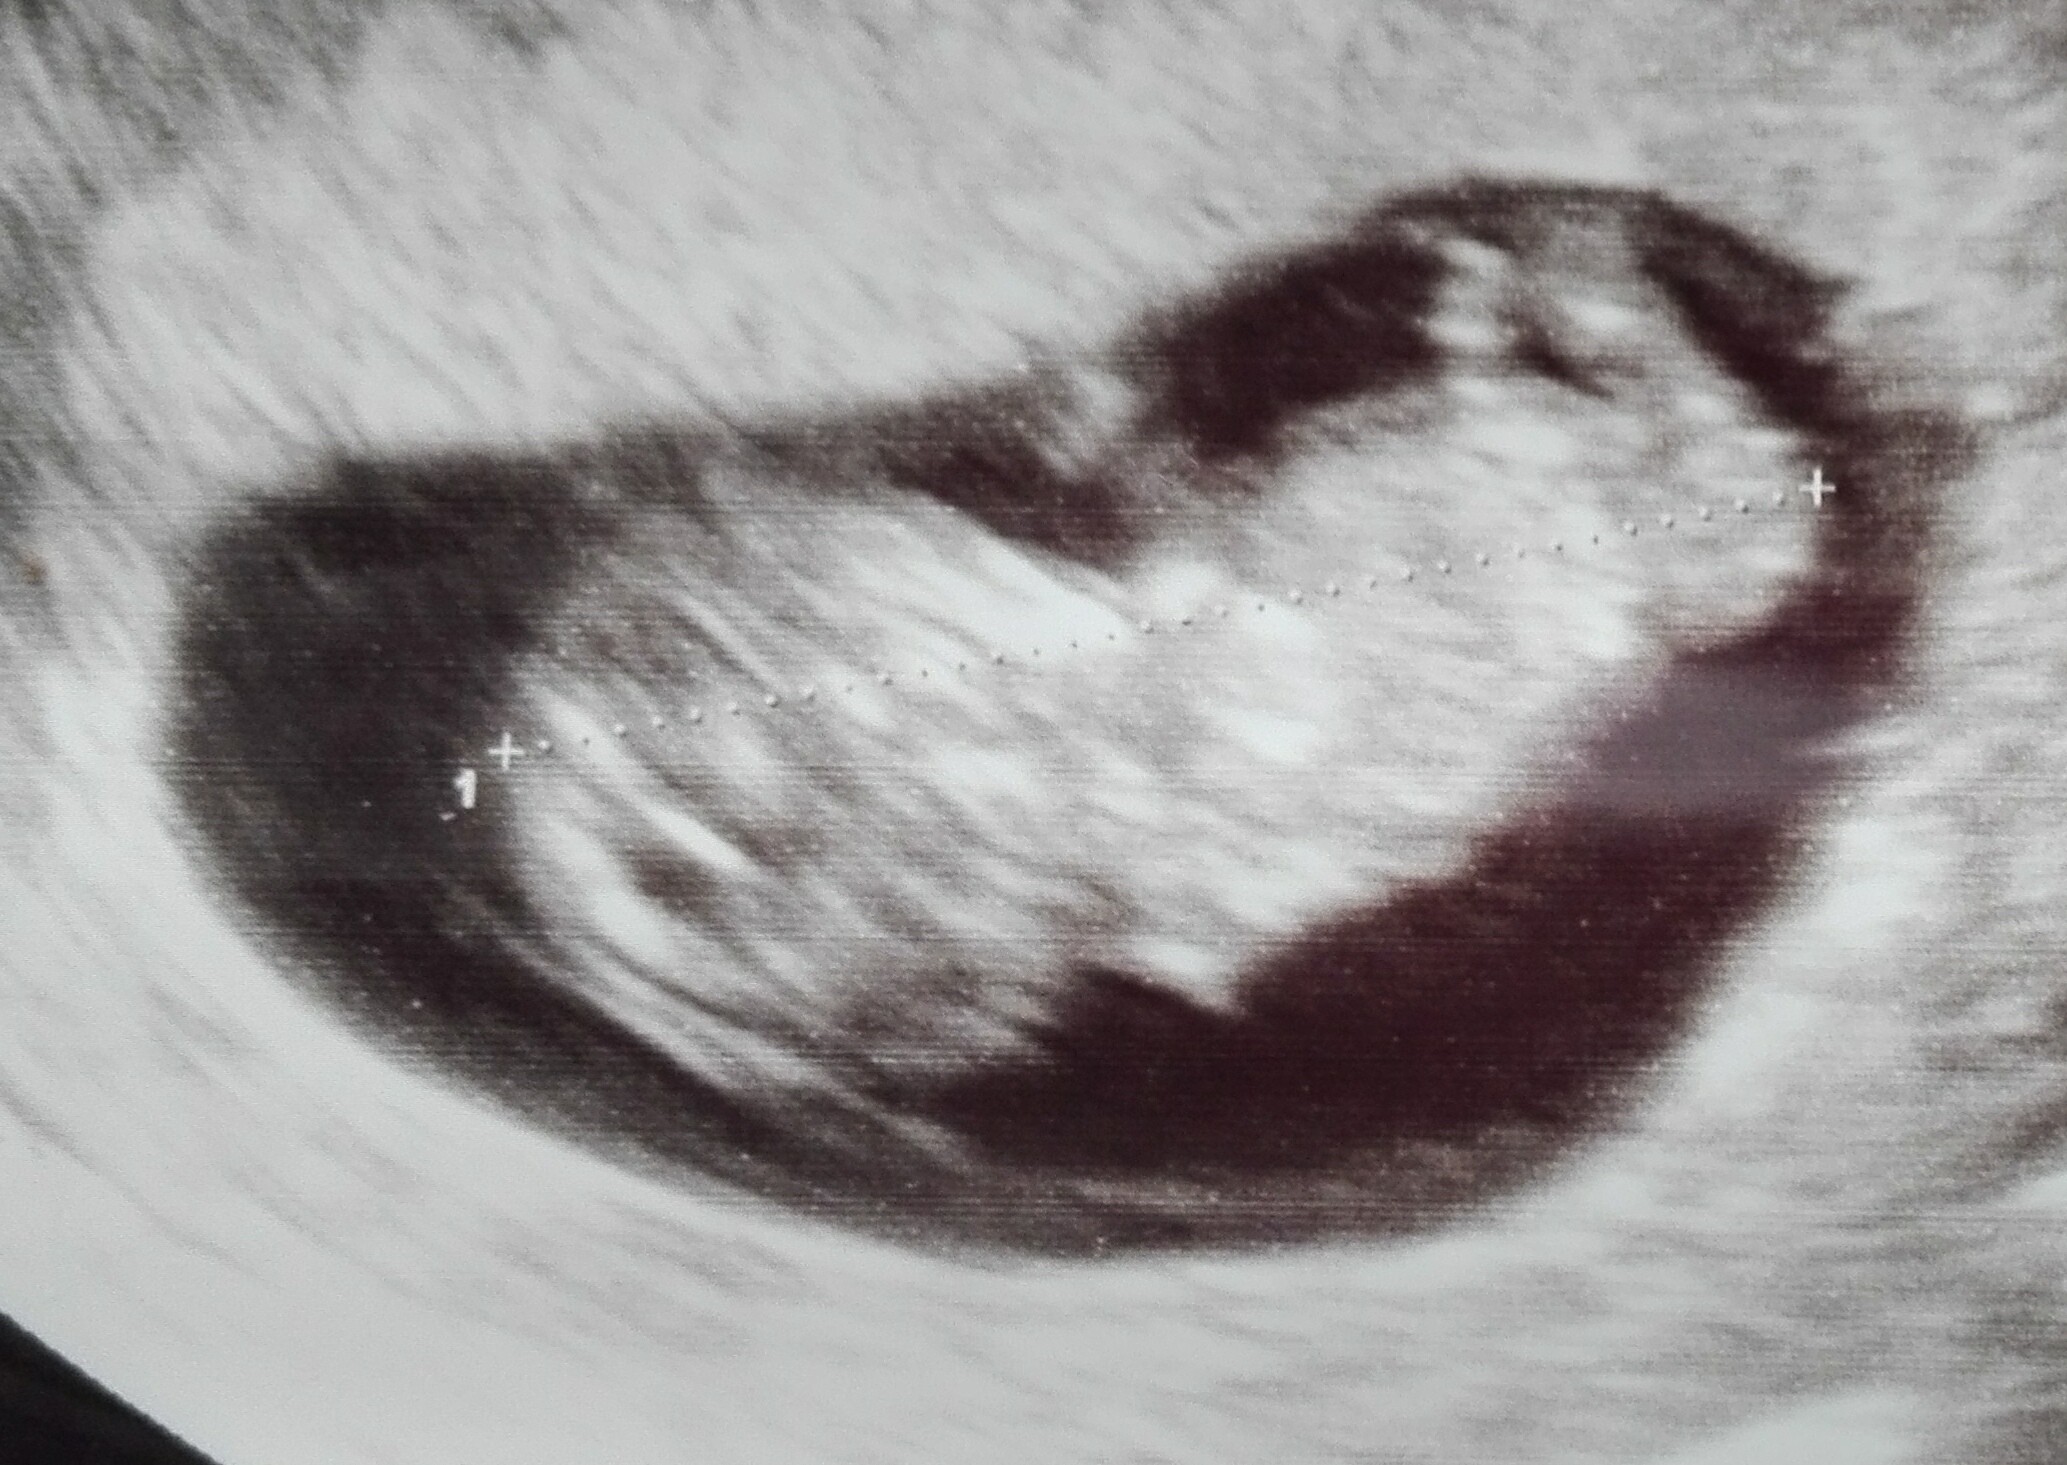

pod sercem noszę: chłopaka!